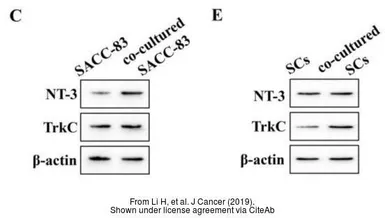

The data was published in the journal J Cancer in 2019. PMID: 31762816